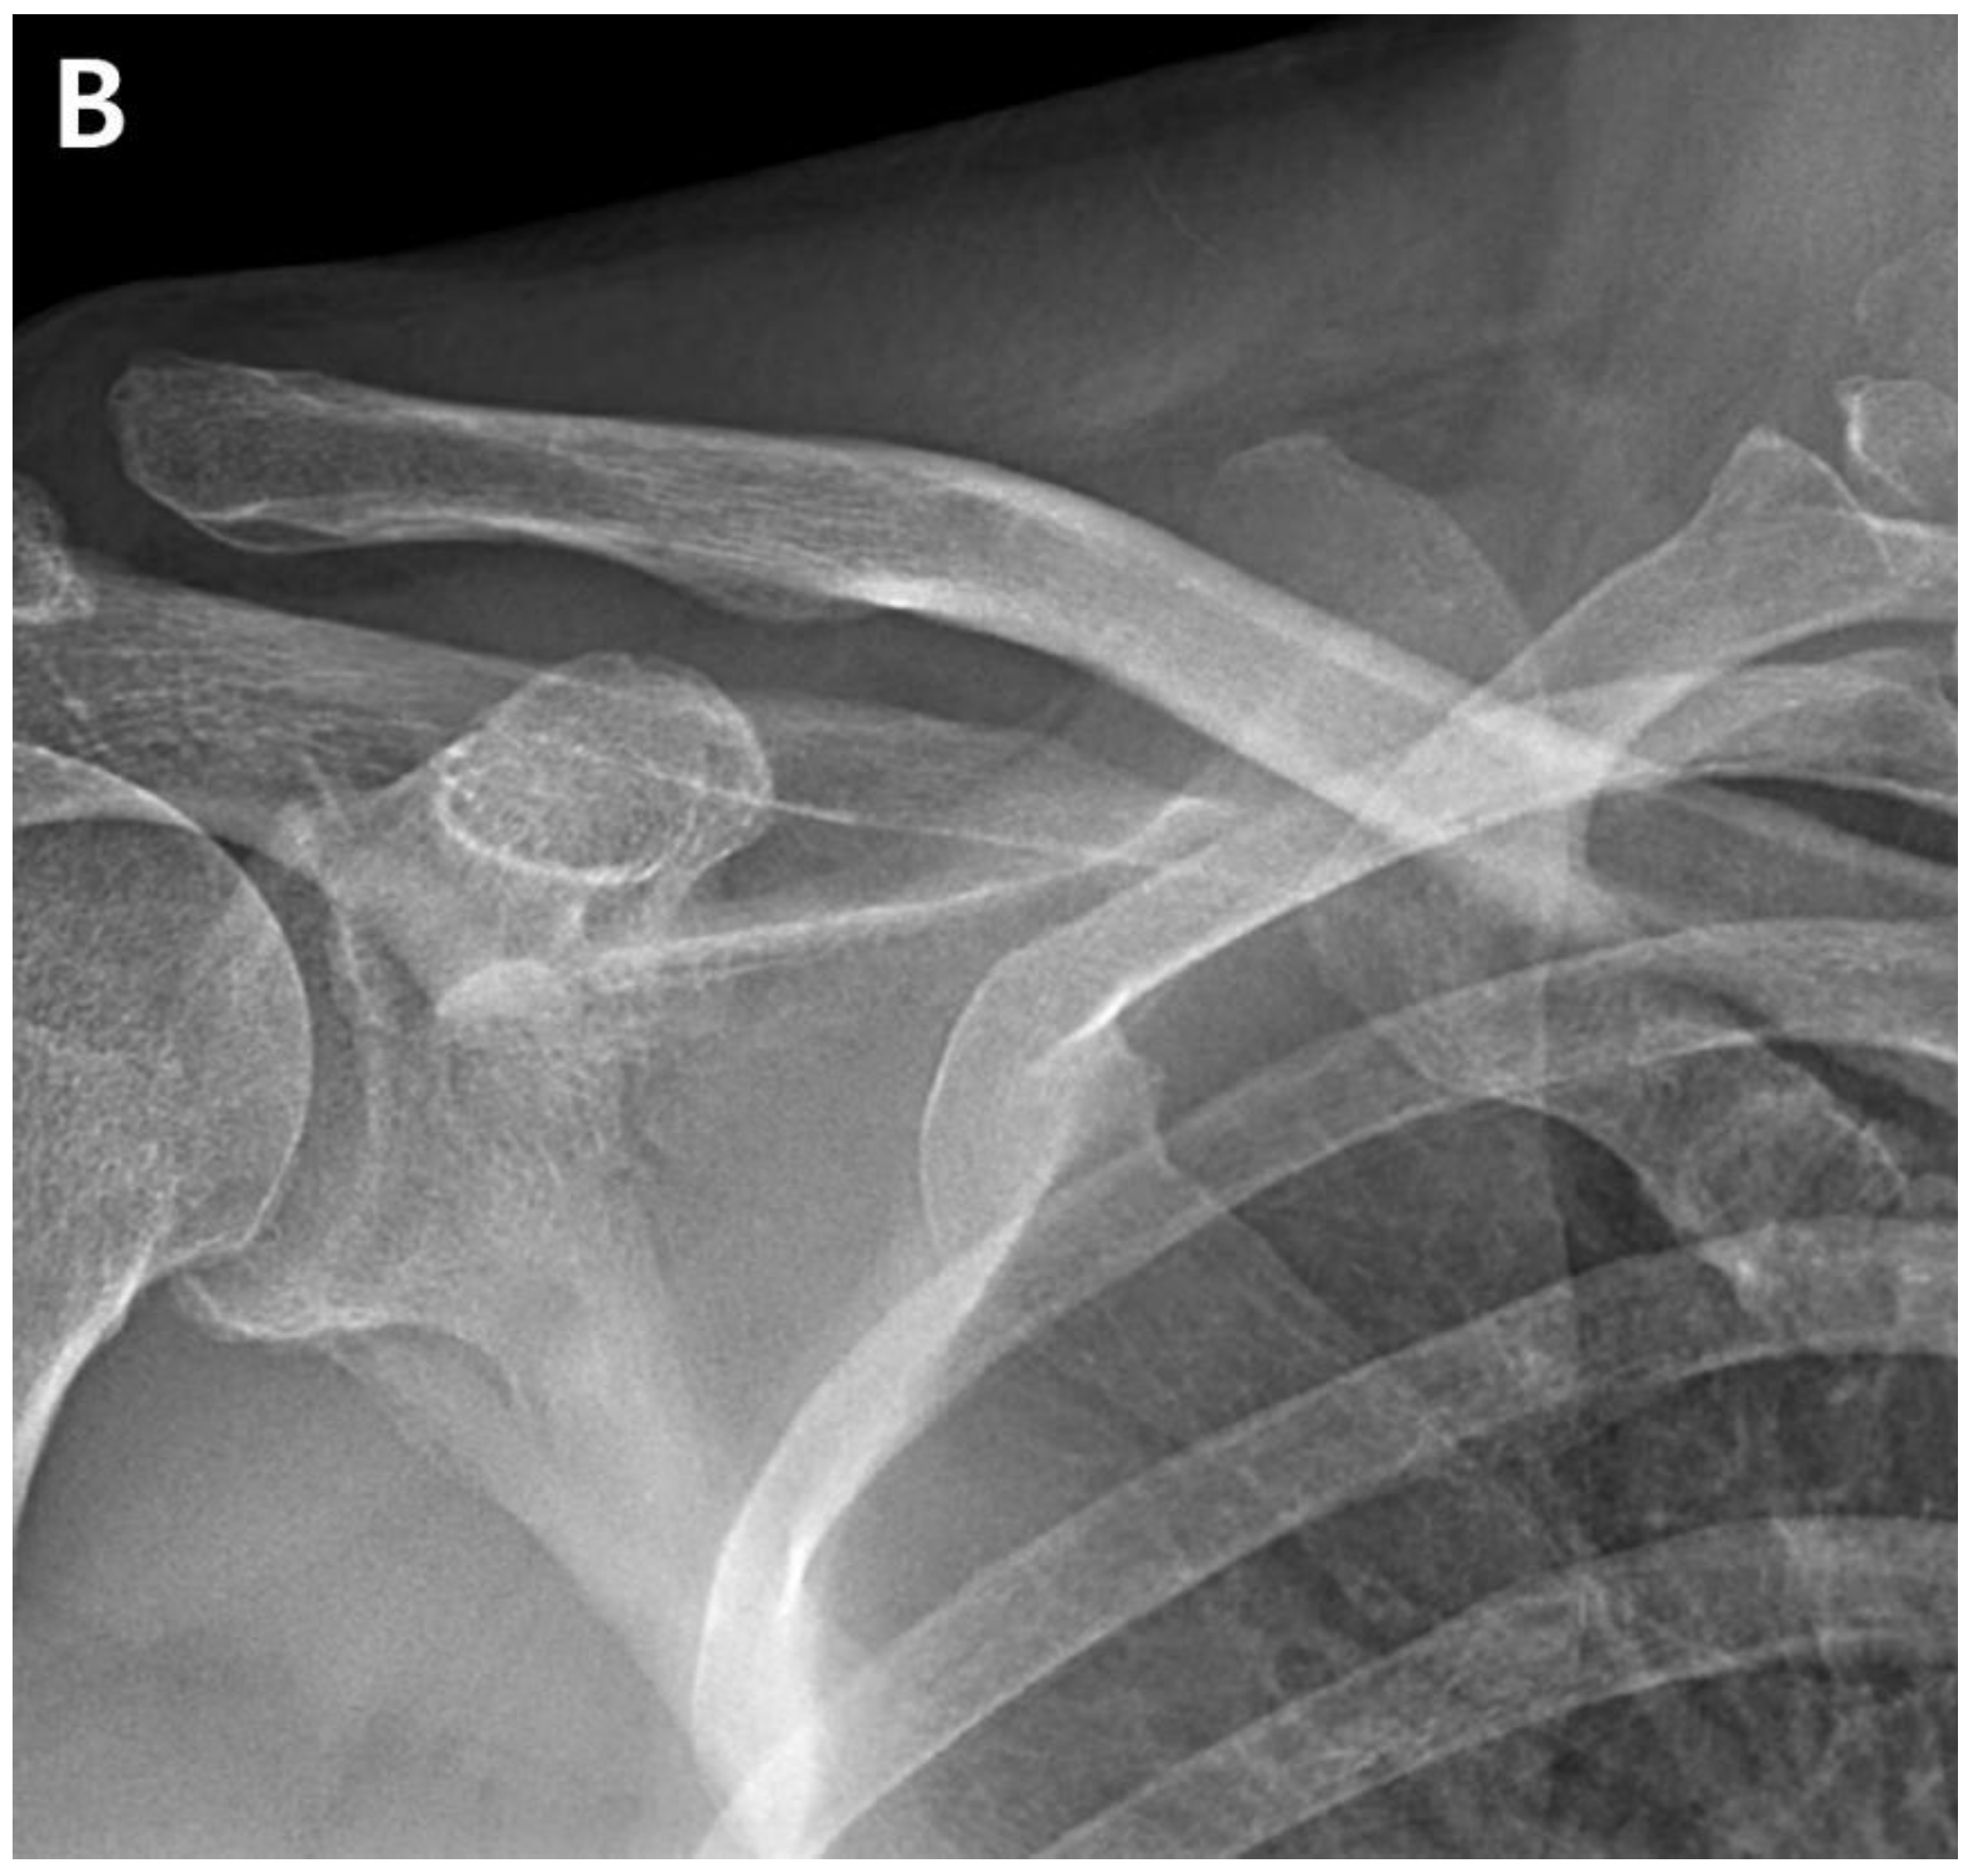

The patient returned to the hospital 21 months after the ACR with right shoulder pain. Plain shoulder anteroposterior radiography and MRI showed a subchondral cyst and a high bone marrow signal on the epiphysis of the superomedial area of the humeral head on T2-weighted images, suggesting avascular osteonecrosis of Cruess stage II (Fig. 4). The patient denied any traumatic injury, radiotherapy, exacerbation of chronic hepatitis, alcohol consumption, or use of other medications. The patient received six intra-articular injections of glucocorticoids during the 15 months of open follow-up at another institution. It is unclear whether the six intra-articular injections were corticosteroids. At 3-years postoperatively, his VAS score was 3, ASES score was 63, and CMS score was 59, indicating increased discomfort. As the patient found the discomfort tolerable in terms of both work capacity and activities of daily living, we decided to maintain the current status and continue observation until osteonecrosis progressed (Fig. 5.)

Figure 4. A. Postoperative plain radiograph obtained at 21 months post-ACR. B. Oblique coronal T1 fat-suppressed MRI. C. Oblique coronal T2 fat-suppressed MRI shows osteolytic changes in the superomedial humeral head. MRI shows cystic changes in the epiphyseal area, but articular congruity remains preserved.